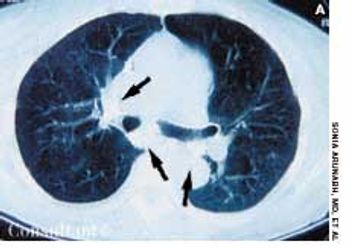

A 72-year-old woman presented for her annual physical examination. She had been treated for tuberculosis 20 years earlier. The patient did not smoke cigarettes; she denied fever, chills, and rigors.